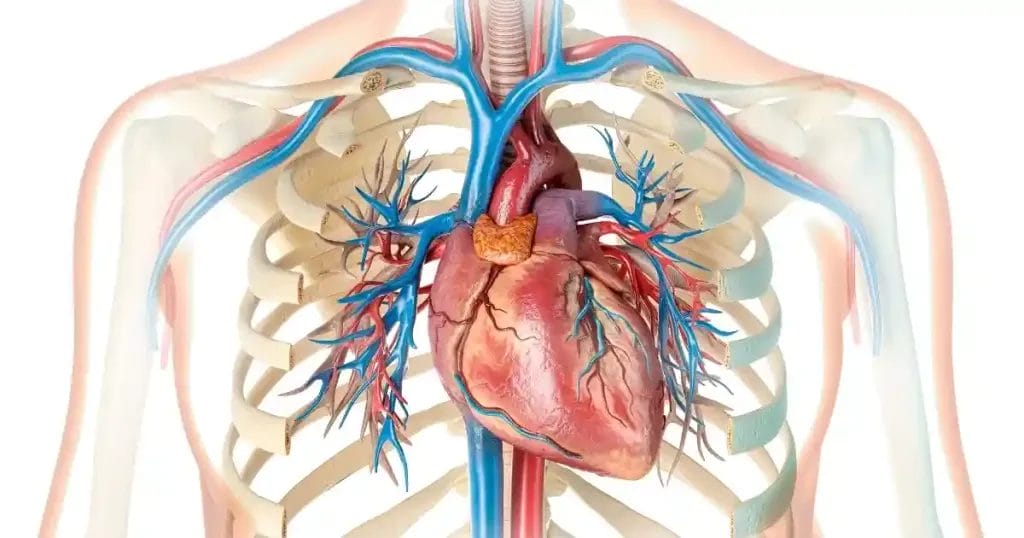

تمدد الشريان الأورطي البطني هو حالة مرضية تتمثل في زيادة غير طبيعية في قطر الجزء السفلي من الشريان الأورطي، وهو أكبر وعاء دموي في الجسم يمتد من القلب إلى البطن، ويزوّد الجسم بالدم المؤكسج، حيث يحدث التمدد نتيجة ضعف تدريجي في جدار الشريان، مما يؤدي إلى انتفاخه وتكون ما يُسمى “أم الدم” أو Aneurysm. يكون هذا التمدد في أغلب الأحيان بدون أعراض واضحة في المراحل المبكرة.

القطر الطبيعي للشريان الأورطي يختلف حسب موقعه في الجسم والعمر والجنس، إلا أن القيم المرجعية المقبولة سريريًا تُعد مؤشرًا هامًا. في البالغين الأصحاء، يبلغ قطر الشريان الأورطي البطني عادة أقل من 3 سنتيمترات، وأي زيادة تتجاوز هذا الحد قد تُعتبر تمددًا أو تضخمًا يستدعي المتابعة.

بينما يختلف قطر الجزء الصدري من الأورطي قليلًا بحسب الموقع الدقيق داخل الصدر، كما أن هذه المقاييس تساعد الأطباء في تشخيص وجود تمدد أو تضخم واعتيار الحاجة للعلاج أو المراقبة الدورية.